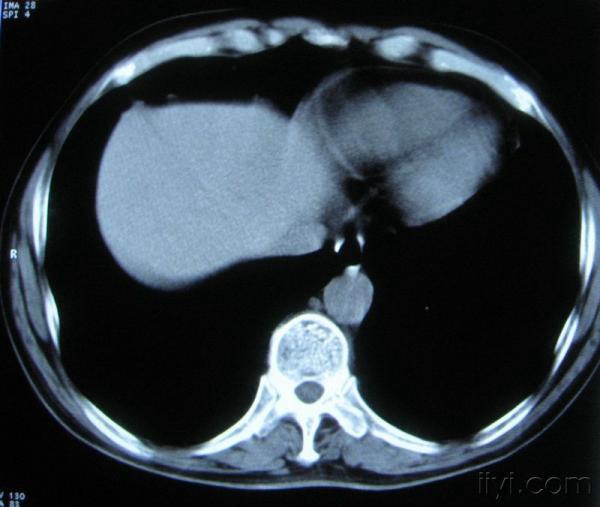

男。60岁,胸片示支气管炎治疗后复查CT。

你指那个肯定是淋巴结,中央系坏死,这很常见,特别在双侧腹股沟会经常看到。这个双侧腋窝及纵隔见多发小淋巴结征。

根据位置考虑应该是淋巴结,密度不均,是因为肿大的淋巴结中心液化坏死